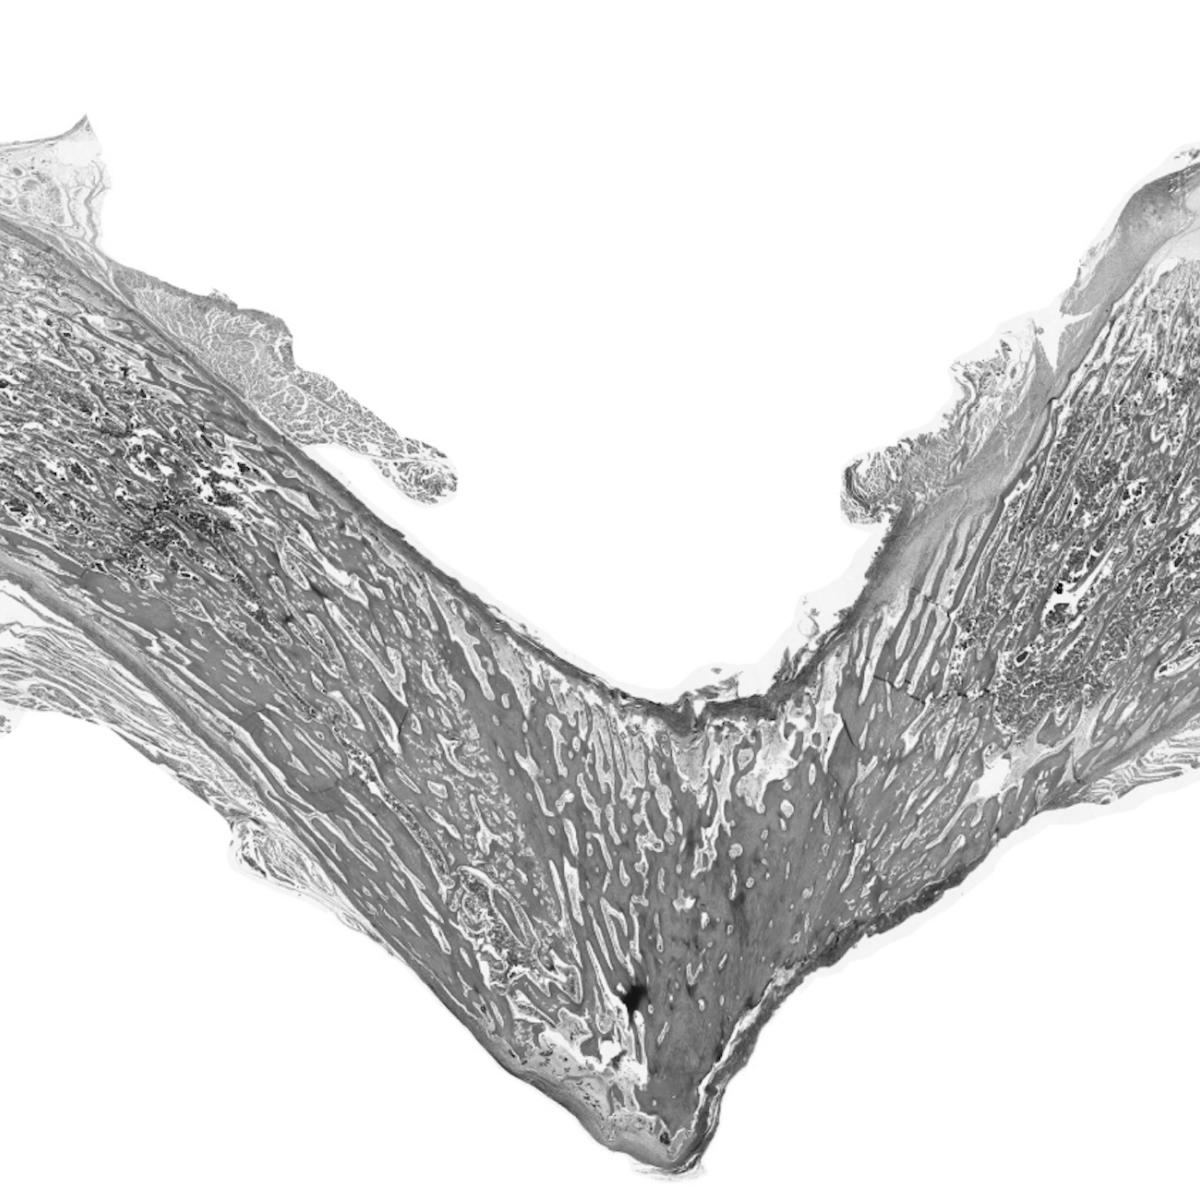

This exhibit reveals the striking imagery of stem cells as a window into the breakthrough research being conducted at UCLA.